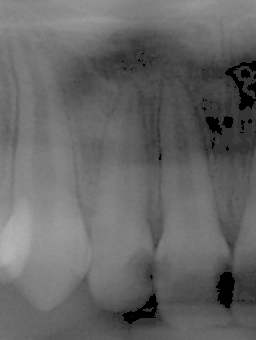

全瓷冠-門齒區根尖囊腫

審美牙科

全瓷冠

全瓷冠-上顎門牙根尖囊腫